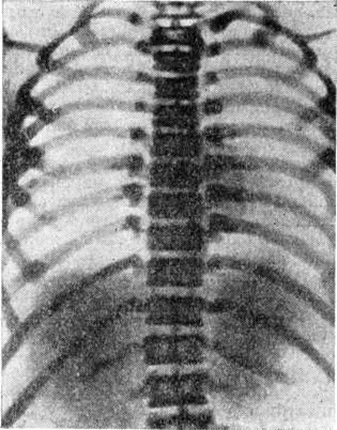

Рис. 4.

Рентгенограмма грудной клетки 10 летнего мальчика с мраморной болезнью (прямая проекция): резко уплотнённая костная структура позвонков.

Рентгенологические изменения обнаруживают в костях черепа, таза, в позвонках, проксимальных отделах бедренной кости, рёбрах, реже — в костях верхних конечностей, кистей и стоп. Форма и размеры костей остаются обычно нормальными. В ряде случаев наблюдается нередкое булавовидное утолщение метафизарных отделов длинных трубчатых костей. Структура костей резко изменена. Вместо обычного трабекулярного, сетчатого рисунка кости приобретают гомогенную плотность, причём наибольшая интенсивность компактного костного вещества отмечается в субкортикальных отделах и на границе эпифиза и метафиза, а также по ходу ростковой зоны апофиза (рисунок 3). В результате неравномерного роста скелета поражённые отделы приобретают своеобразный рисунок, образованный параллельно расположенными полосами и полукольцами. В костях черепа в первую очередь поражаются кости, имеющие хрящевое происхождение. Наряду со склерозом костной ткани отмечается сужение каналов, через которые проходят черепные нервы, придаточные пазухи, носа облитерируются. Своеобразный вид приобретают тела позвонков, центральная часть которых просветлена, а по ходу замыкающих пластинок образуются плотные широкие полосы (рисунок 4). Темпы энхондрального окостенения скелета-нередко нарушены, что. проявляется в запаздывании появления ядер окостенения и синостозирования эпифизов в костях кистей и стоп.